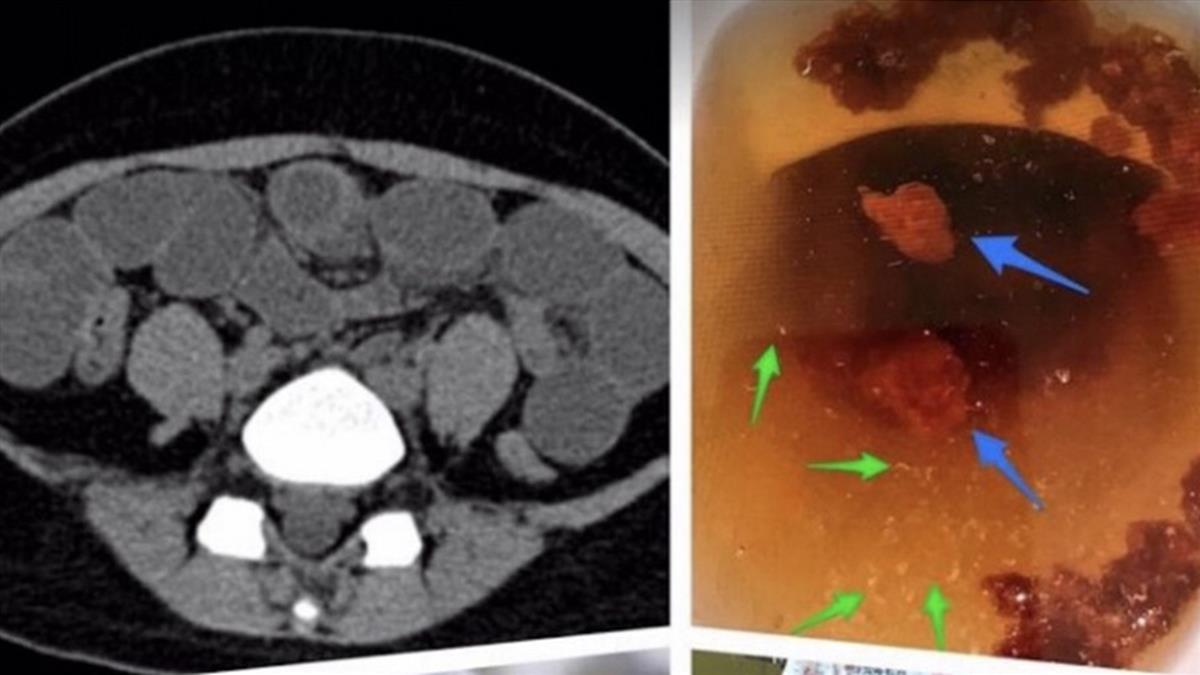

李宏昌說,今年初曾收治一名16歲少女,腹痛好幾個月都沒有好轉,甚至愈來愈嚴重,每天都吐出黃綠色物質,就醫後確診腸阻塞,但卻遲遲找不出阻塞原因,內視鏡一看發現少女腸子全被棉花塞住。

進一步詢問之下,少女才坦言因同住父親常嫌她腿粗,她為了減肥竟嘗試網路上流傳的「吃棉花減肥法」,短短1年內將一整條棉被吞下肚,最近甚至開始吃起圍巾,後來以瀉藥治療才順利將體內棉花排出。